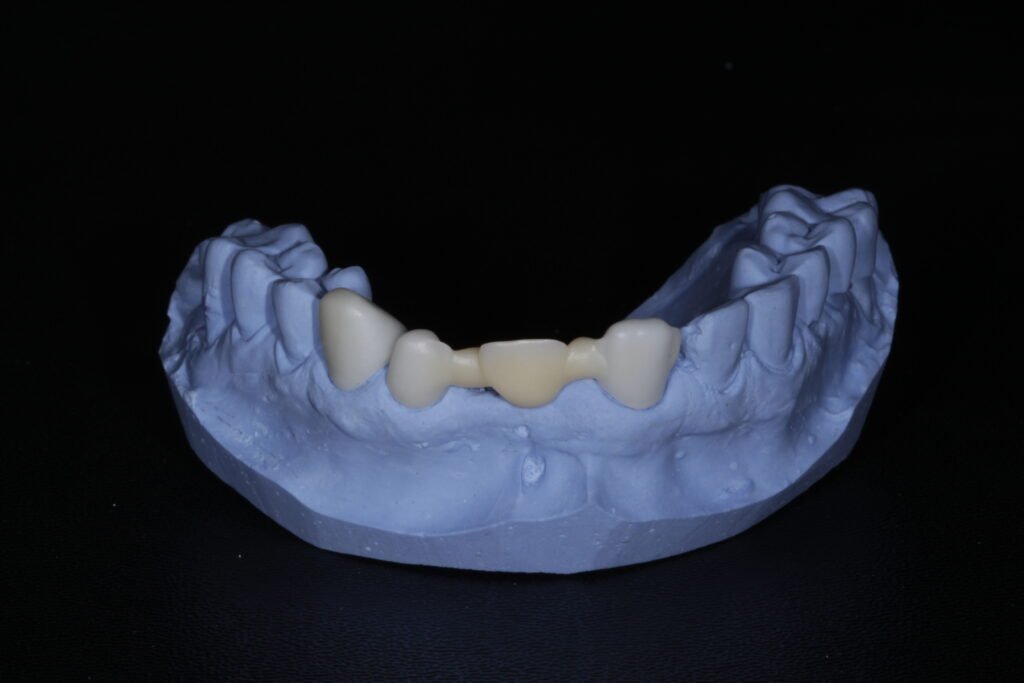

Diseño digital CAD/CAM

Con la experiencia de nuestro equipo y la alta tecnología de VirtuoLab transformamos la precisión de tus escaneos en arte. Elaboramos diseños personalizados según la anatomía y oclusión de tus pacientes.

Prótesis fija, removible e implantosoportada

Por último, el diseño digital se materializa a través del fresado e impresión de alta precisión con maquinarias automatizadas. Garantizando resultados finales con estética superior y ajuste milimétrico en todos tus trabajos.